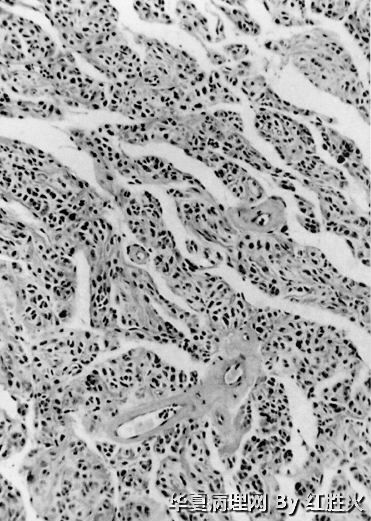

2、低倍镜下见界限清楚,中央囊变,具有肿瘤细胞密集区和疏松黏液样变区,局部有模糊结节状。

3、高倍镜下观察到以下特点:(1)中等大小的血管呈管壁玻璃样变性;(2)细胞核有深染、不规则形,但罕见核分裂,类似于退变性核;(3)细胞呈卵圆形、圆形或多角形,粘液样变区可见细胞界限较清,排列方式巢、索状,细胞浆较丰富,红染;(4)可见纤维性中心的菊形团样结构。